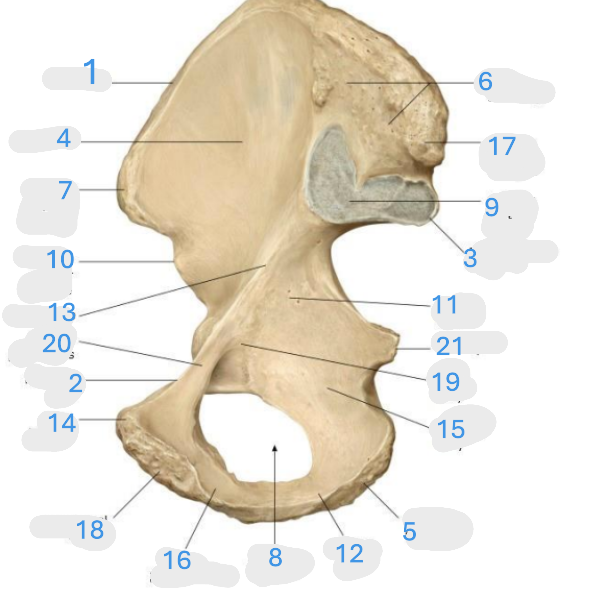

Where is the iliac crest

1

where is the sacral canal

2

Where is the iliac tubercle

3

Where is the outer lip

4

Where is the inner lip

5

Where is the iliac fossa

6

Where is the pectineal line (pecten pubis)

7

Where is the sacroiliac joint

8

Where is the ischial spine

9

Where is the iliac tuberosity

10

Where is the promontory

11

Where is the arcuate line

12

Where is the anterior superior and inferior iliac spine

13

Where is the intermediate line

14

Where is the ala of the sacrum

15

Where is the coccyx

16

Where is the pubic crest

17

Where is the pubic tubercle

18